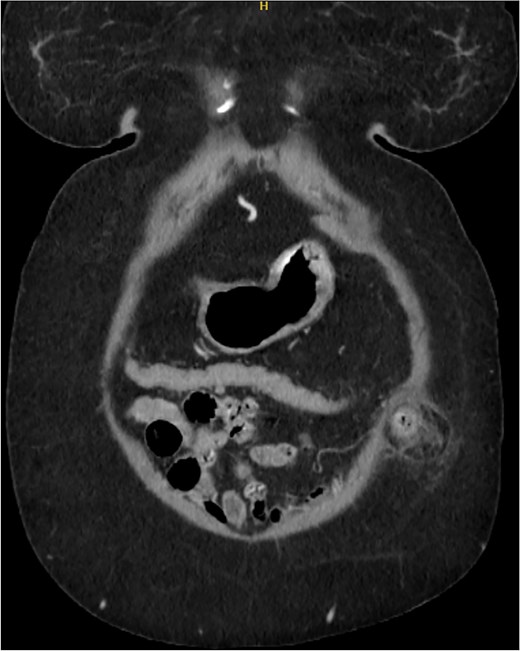

A 76-year-old female with a medical history of type 2 diabetes mellitus (controlled with oral medications), hypertension (on two medications), hyperlipidemia (on atorvastatin), and recently diagnosed Alzheimer’s disease (started on memantine) presented to the emergency department with severe left-sided abdominal pain of 2 days’ duration. The pain began gradually but worsened significantly in the last few hours. It was associated with a bulging mass in the abdomen that was tender and painful to touch. The patient reported that the swelling had been present for 2 years, intermittently reducible with minimal exertion. However, since the previous day, it had become irreducible and increasingly painful, particularly after a failed attempt to reduce it manually at home. She also admitted to chronic constipation for years, usually treated with oral laxatives, though she had not been compliant with them recently. Her surgical history included a laparoscopic cholecystectomy combined with paraumbilical hernia repair using mesh 3 years ago. Upon examination by the on-call surgical team, the patient was afebrile with stable vital signs. Her abdomen was distended, and a 7 × 7 cm irreducible, tender mass was noted over the left side. An urgent computed tomography (CT) scan of the abdomen and pelvis with intravenous and oral contrast revealed a left lateral ventral abdominal hernia traversing the left lateral oblique muscles. The hernia sac contained omental fat and an inflamed diverticulum of the transverse colon, with surrounding inflammatory changes. The defect measured 1.4 × 1 cm, and the hernia sac measured 6.7 × 4.2 × 4 cm. No free fluid, fluid collections, or pneumoperitoneum were identified (Figs 1–3).

Sagittal section of CT abdomen and pelvis showing the ventral hernia.